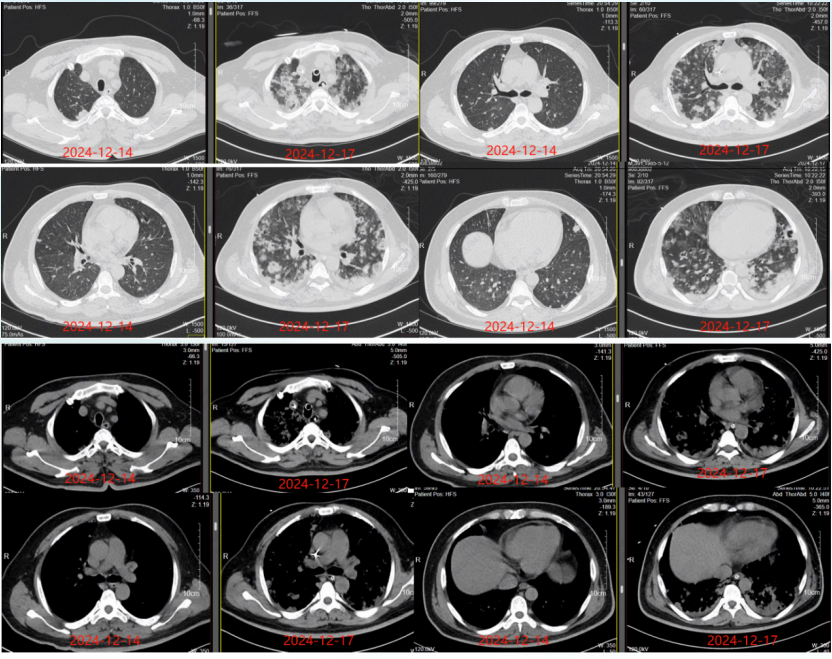

患者2天前无明显诱因下出现发热,未测体温,伴咳嗽咳痰,白色痰,较多,易咳出,伴乏力,伴全身酸痛,伴呕吐1次,呕吐物为胃内容物,无畏寒咽痛头痛头晕等不适,遂来我院急诊,查急诊血常规+超敏C反应蛋白(hs-CRP):白细胞计数(WBC)16.88×109/L(↑),中性粒细胞计数(NEU)15.65×109/L(↑)hs-CRP 244.5 mg/L(↑)2024年12月14日行加急胸部CT示:双肺弥漫斑块、结节影,建议CT增强检查心包少量积液(图1)。患者为求进一步诊治,急诊拟“肺炎”收住入院。

图片

1  患者胸部CT(2024-12-14)